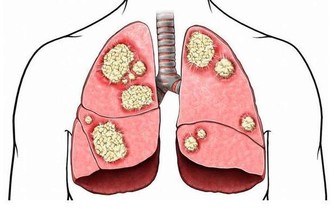

1、殘留的尿液容易反流,此時尿道的細菌會侵入,從而誘發慢性前列腺炎。

2、加重原有的前列腺病症,時間長了使膀胱出口梗阻症狀加重。

如果尿頻的同時,還伴有尿急、尿痛等不適,應警惕是否患上泌尿系統感染。

男性的排尿時間如果明顯變長,而且有滴滴答答、尿不盡的感覺,或者出現尿無力、排尿困難,中老年男性起夜增加等症狀,都要懷疑是否患上前列腺疾病。

排尿的時候,如果發現尿液泡沫增多,尤其是晨起第一泡尿,這可能是蛋白尿,大多由腎髒病所引起,此時要盡快去醫院做尿常規檢查,關注尿蛋白是否增加。